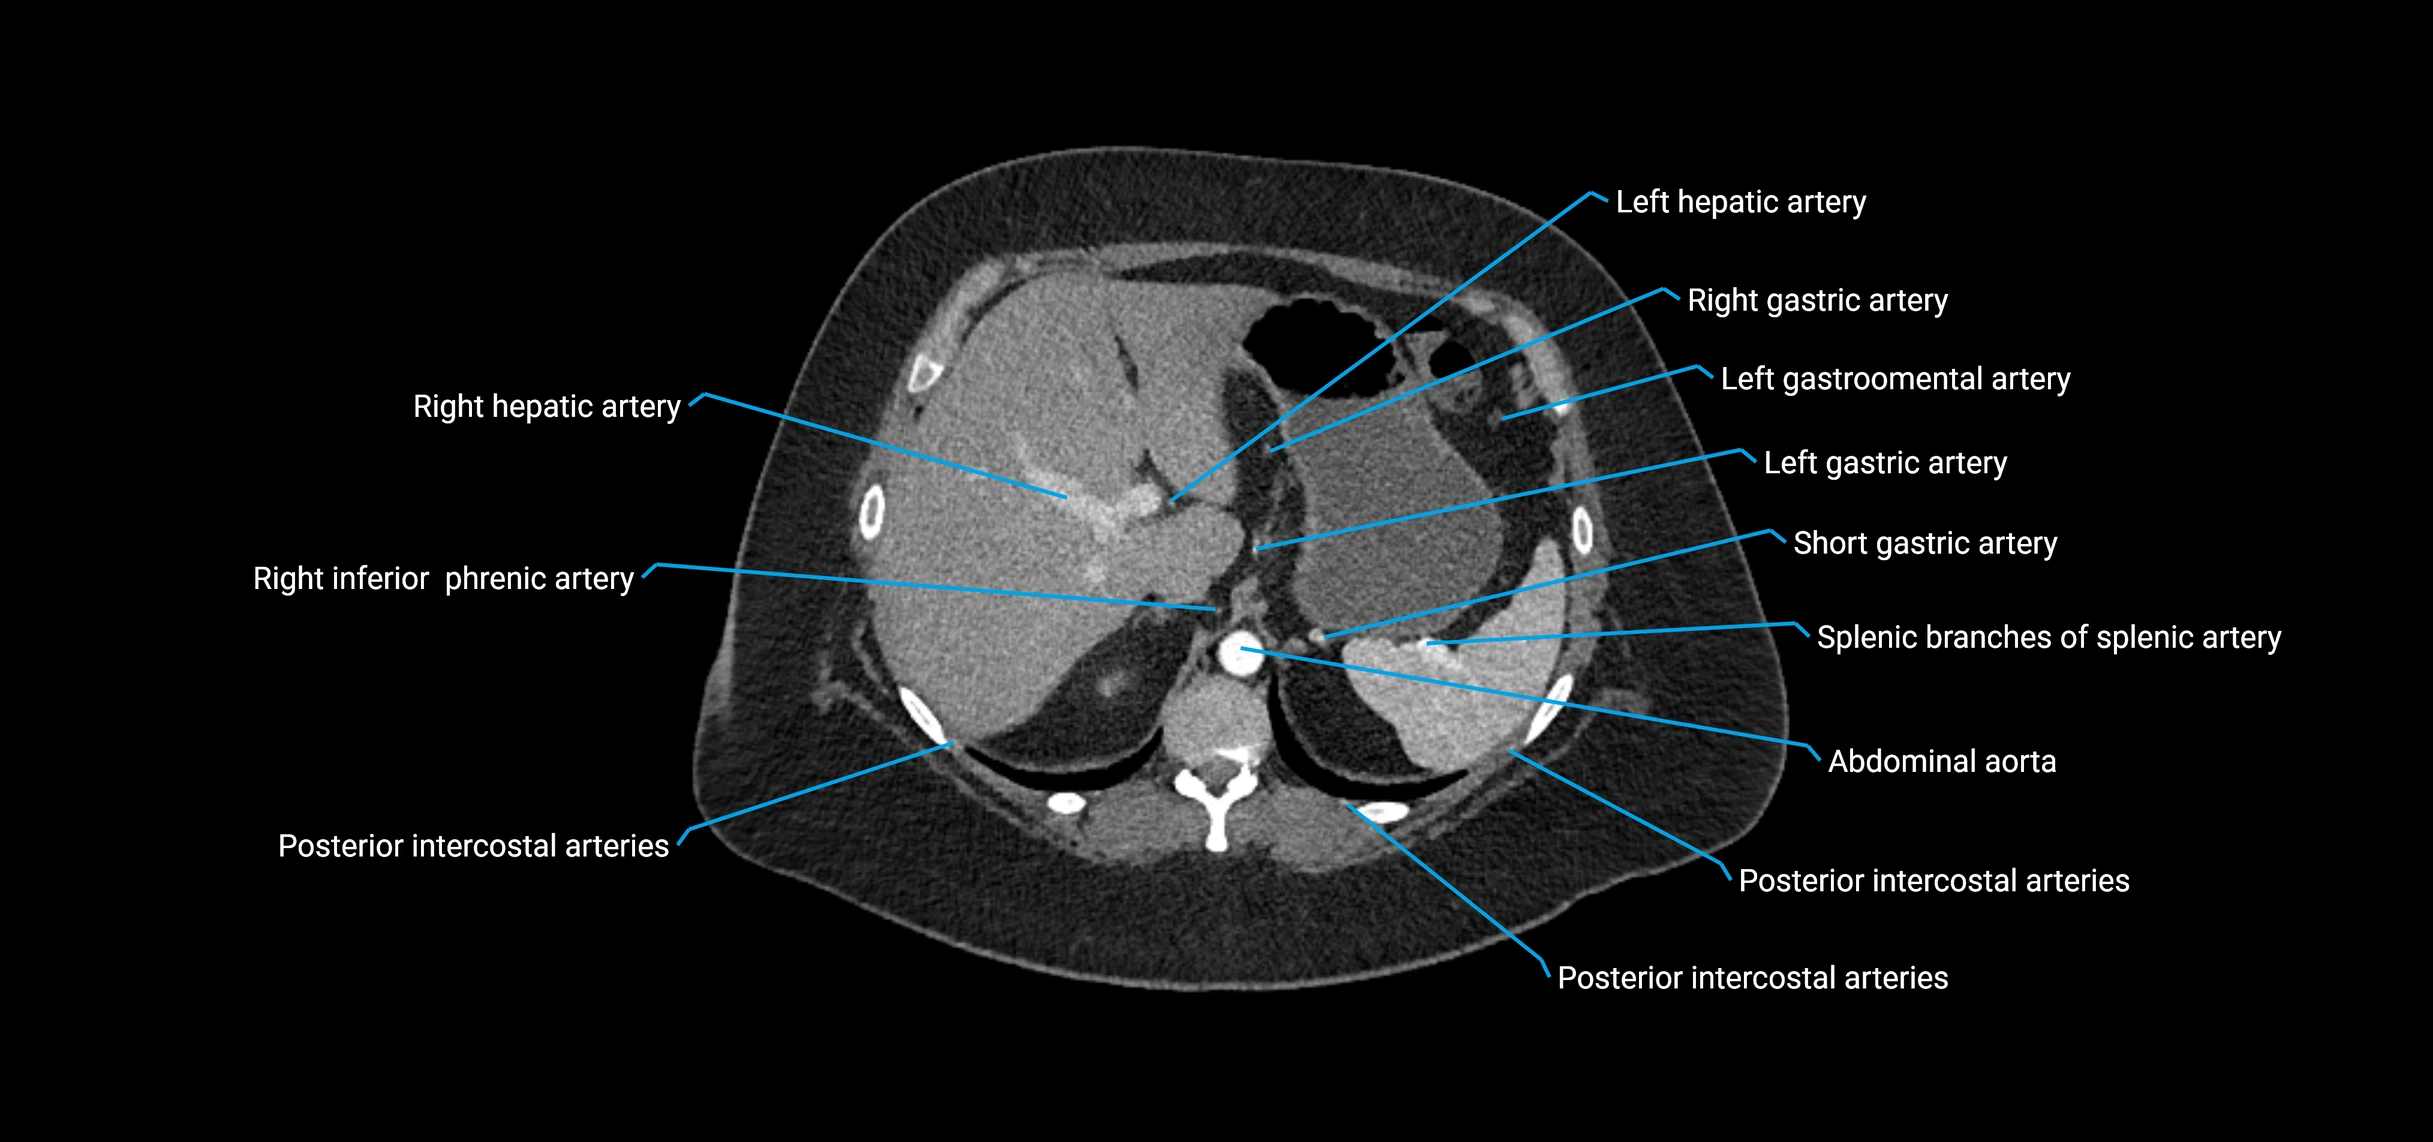

The abdominal aorta is the continuation of the thoracic aorta, beginning at the level of the aortic hiatus of the diaphragm (T12 vertebra) and terminating at the level of the L4 vertebra where it bifurcates into the right and left common iliac arteries. It lies slightly to the left of the midline and courses anterior to the vertebral bodies, surrounded by the retroperitoneal structures of the abdomen.

The abdominal aorta gives off numerous visceral and parietal branches, supplying the abdominal organs, pelvic structures, and lower limbs. It is the main conduit of oxygenated blood from the heart to the abdomen and lower body. The aorta is clinically significant as the common site of aneurysm, dissection, atherosclerosis, and traumatic injury.

Branches

• Unpaired visceral branches: celiac trunk, superior mesenteric artery (SMA), inferior mesenteric artery (IMA)

• Paired visceral branches: middle suprarenal arteries, renal arteries, gonadal arteries (testicular or ovarian)

• Parietal branches: inferior phrenic arteries, lumbar arteries, median sacral artery

CT Appearance

Contrast-enhanced CT (CTA):

• Gold standard for abdominal aortic imaging

• Provides excellent detail of lumen, wall, aneurysm, thrombus, and branch vessels

• Multiplanar and 3D reconstructions help in aneurysm measurement, stent graft planning, and dissection evaluation

CT images

image